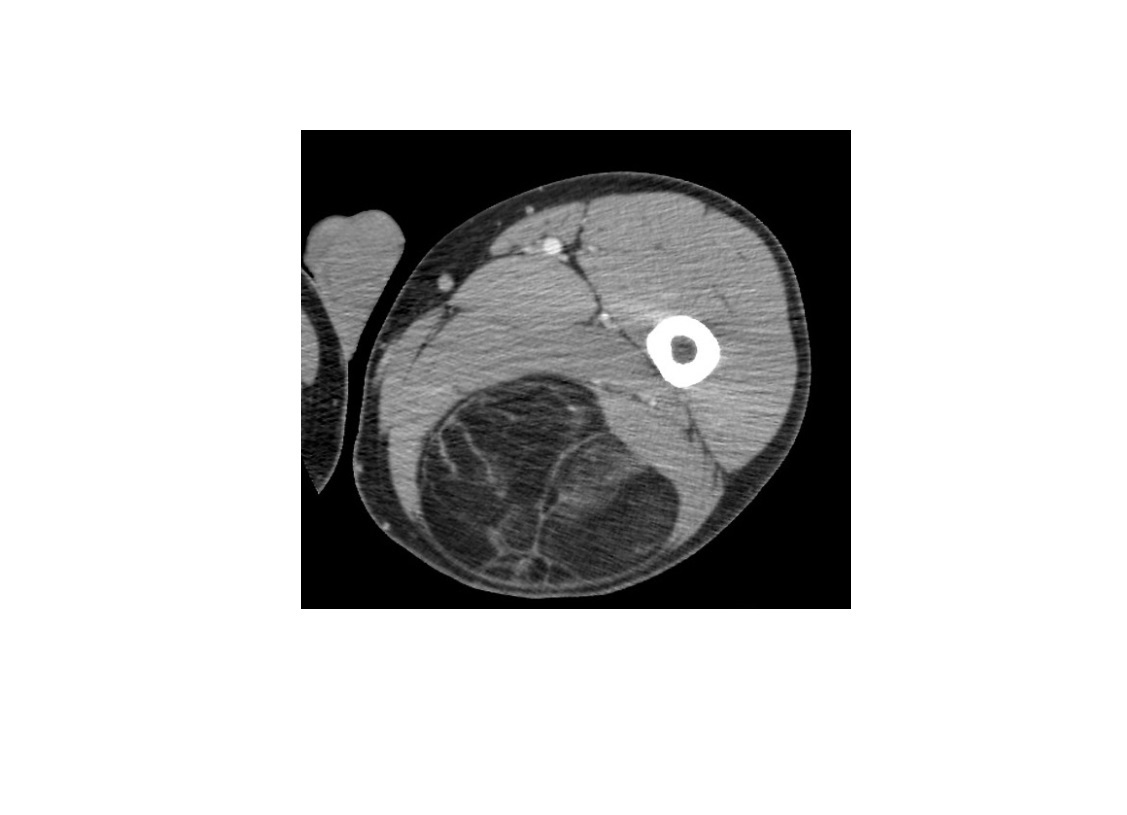

22

Q

A

Osteoid osteoma

Cortically based

peripheral sclerosis and central with nidus

**nidus > 2cm = osteoblastoma **

= Posterior elements

Nb** Osteoblastoma can have have soft tissue expansion/involvement**

Double density bone scan